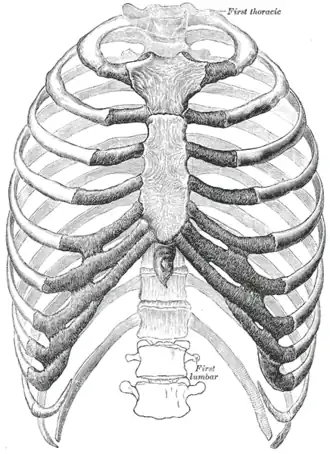

As costelas humanas.

As costelas humanas. -